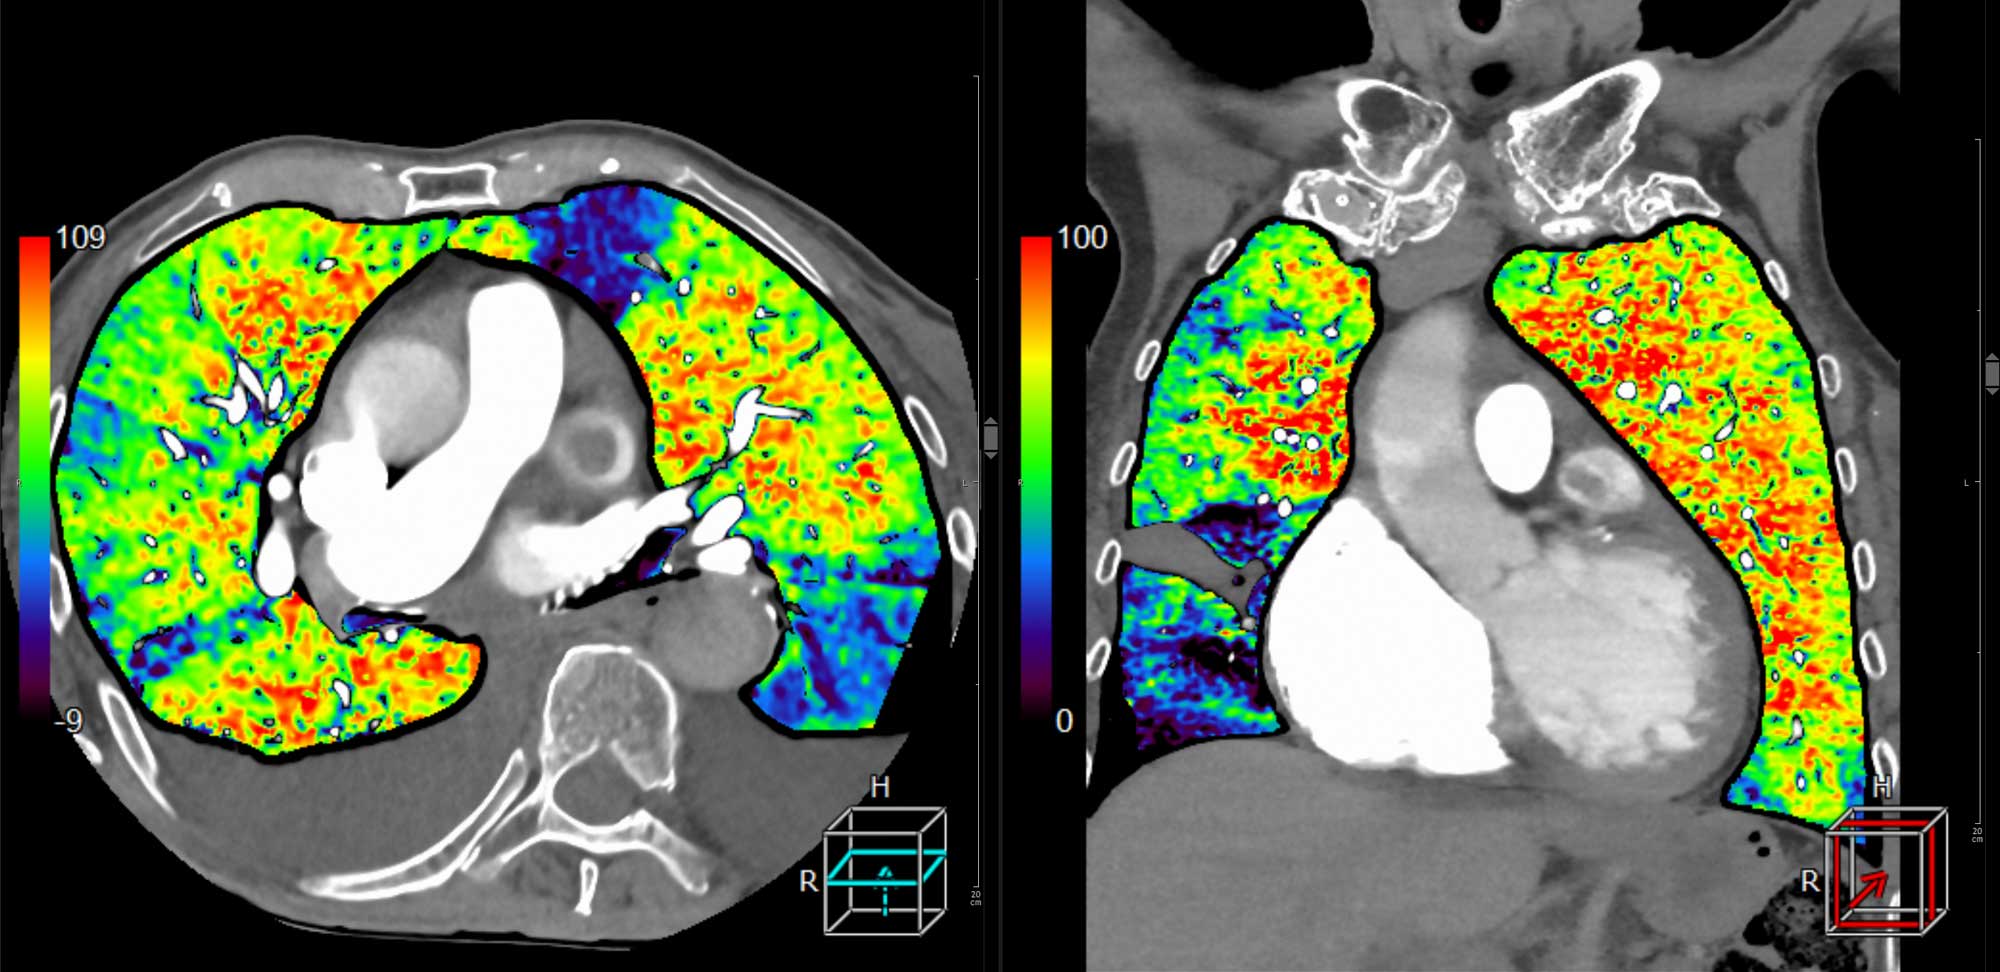

. Ein CT-Scan der Lunge in zwei Ansichten, mit farbcodierten Bereichen zur Darstellung der Gewebedichte.

Perfusionsstudie mit Dokumentation Embolie-bedingter Mikrozirkulationsstörungen (blau)